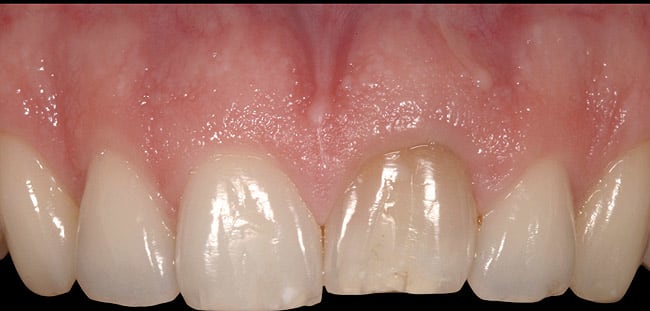

This was an esthetic high-risk case due to extremely high patient expectations and existing distal papilla bone loss. The patient, who had sustained a vertical root fracture of the right central incisor during a snowboarding accident, also presented with a facial fistula at mid-root level (Figure 4 and Figure 5).

The decision was made to use orthodontics to correct the occlusion and tooth position of the adjacent teeth. It was also decided to force erupt the hopeless lateral incisor and central incisor to improve the missing interproximal bone on the distal surface of the incisor. Forced eruption of the incisor also would move the fracture more coronal and create a healthy environment prior to implant placement. Treatment goals were to decrease inflammation and the fistula, overcompensate for recession, and improve osseous levels. The sinus tract progressively decreased as the tooth was force erupted (Figure 6). At the time of immediate placement, a CTG was also performed to preserve the facial ridge profile along with a custom healing abutment (Figure 7).

A provisional was placed on the implant at 3 months, which, like the custom healing abutment, continued to provide soft-tissue support. At 5 years, the gingival health levels were maintained, along with a highly esthetic outcome (Figure 8).